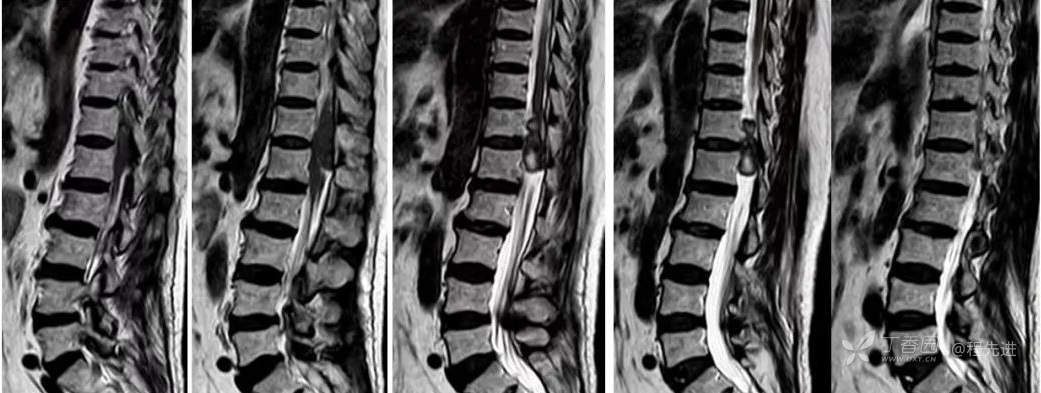

MR: